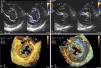

Case reportA 52-year-old man was referred for valve surgery due to severe mitral regurgitation secondary to a mitral cleft and moderate aortic regurgitation through a bicuspid aortic valve. Two-dimensional transesophageal echocardiography (2D TEE) showed a single AV junction with a trifoliate left valve: one mural, one anterosuperior and one posteroinferior, with a ‘cleft’ oriented towards the interventricular septum in the zone of apposition (Figure 1A and B). The papillary muscles were displaced laterally, next to the mural leaflet commissures with bridging leaflets. Three-dimensional (3D) TEE provided detailed anatomical information (Figure 1C and D). No evidence of interatrial or interventricular communication, usually characteristic of AVSD, was observed.

(A and B) Two-dimensional transesophageal echocardiography, transgastric view, showing trifoliate configuration of the left AV valve and the ‘cleft’ (*) in diastole (A); mitral regurgitation from the ‘cleft’ in systole (B); (C and D) real-time three-dimensional zoom, cropped images: in diastole, atrial view (C) and ventricular view (D), the morphology of the three leaflets of the left AV valve can be seen in detail, as well as the septal orientation (towards the right ventricle) of the ‘cleft’. Abnormal chordal attachments linking the edges of the ‘cleft’ to the interventricular septum can be clearly seen in ventricular view (arrow). Other features of a left atrioventricular valve can be seen – elliptical annulus and small mural leaflet. 1: anterosuperior leaflet; 2: posteroinferior leaflet; 3: mural leaflet; AOV: aortic valve; LVOT: left ventricular outflow tract; TV: tricuspid valve.